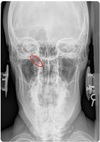

3

APOM ANATOMICAL LANDMARKS

maxillary sinus

29

frontal sinus

30

nasal aperature

31

nasal spine + septum

32

lower teeth

33

upper teeth

34

mandible

35

jugular process

36

A-P open mouth

rim of foramen magnum

37

anterior arch c1

38

posterior arch c1

39

A to P open mouth

lateral mass of c1

40

transverse process c1

41

medial inferior tip of occipital condyles

42

mastoid air cells

43

A-P open mouth view

pedicle shadow c2

44

spinous process c2

45

eop-iop

46

atlantal-axial joint space

47

vertebral bodies c2-c7

48

inferior articular surface c1

49

superior articular surface c1

50

A-P cervical

uncinate process of cervical vertebra

51

occipital-atlantal joint space

52

odontoid process